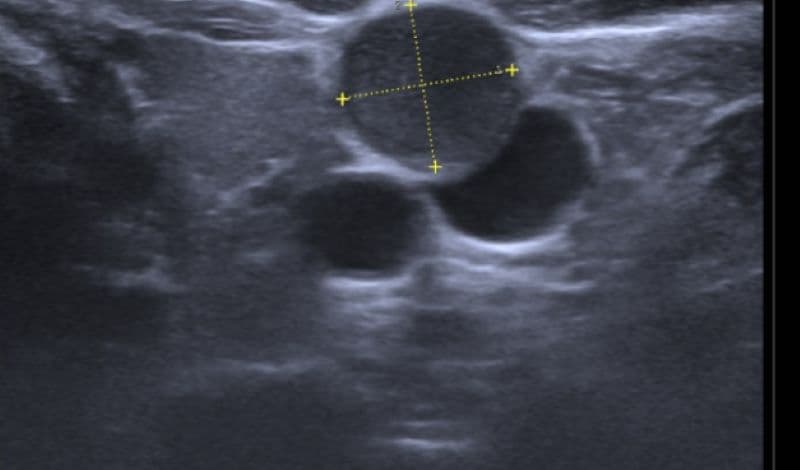

Khi quan sát hạch lao trên siêu âm, bác sĩ thường thấy hạch có kích thước to hơn bình thường, đường kính có thể từ 1cm đến vài cm. Hạch thường có dạng bầu dục hoặc tròn, tuy nhiên kích thước giữa các hạch trong cùng một vùng có thể không đồng đều.

Trong nhiều trường hợp, không chỉ xuất hiện một hạch đơn lẻ mà có thể có nhiều hạch cùng tồn tại, tập trung thành từng cụm ở vùng cổ hoặc thượng đòn. Đây là một trong những biểu hiện sớm gợi ý tình trạng lao hạch.

Một đặc trưng nổi bật trong hình ảnh hạch lao trên siêu âm là sự xuất hiện của vùng giảm âm hoặc trống âm ở trung tâm hạch. Những vùng này có thể không đồng nhất, đôi khi gồm nhiều ổ nhỏ nằm sát nhau.

Đây chính là biểu hiện của hoại tử bã đậu – đặc điểm điển hình của bệnh lao. Sự hiện diện của hoại tử trung tâm giúp phân biệt hạch lao với các hạch viêm thông thường.

Hạch dính thành mảng

Một điểm đáng chú ý khác của hạch lao trên siêu âm là các hạch có xu hướng dính vào nhau thay vì nằm tách biệt. Chúng có thể liên kết thành chuỗi hoặc mảng lớn.